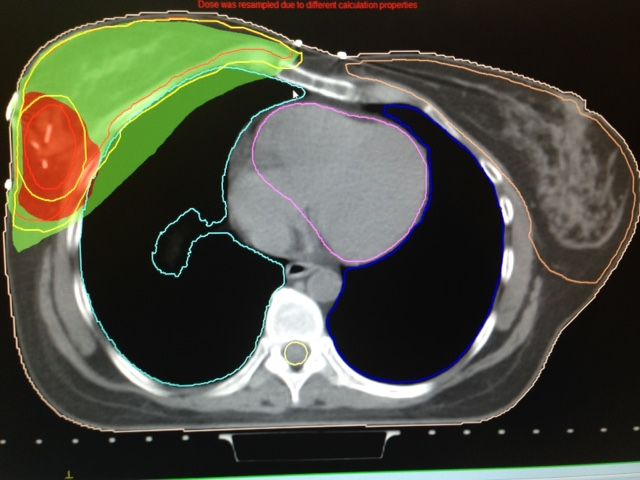

• Terapia de arco volumetrico modulado (VMAT)